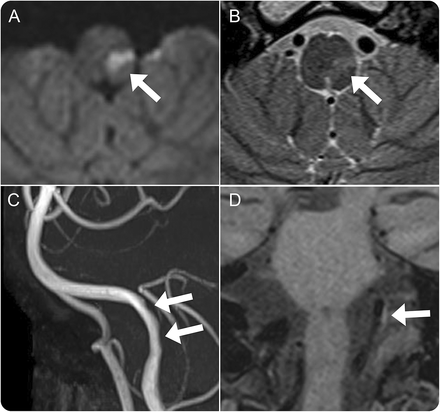

图1

磁共振成像和磁共振血管造影术的髓质和椎动脉

Diffusion-weighted和t2加权图像显示急性梗死的左边侧髓质(A, B)。磁共振血管造影术和黑血MRI显示左椎动脉的解剖(C, D)。